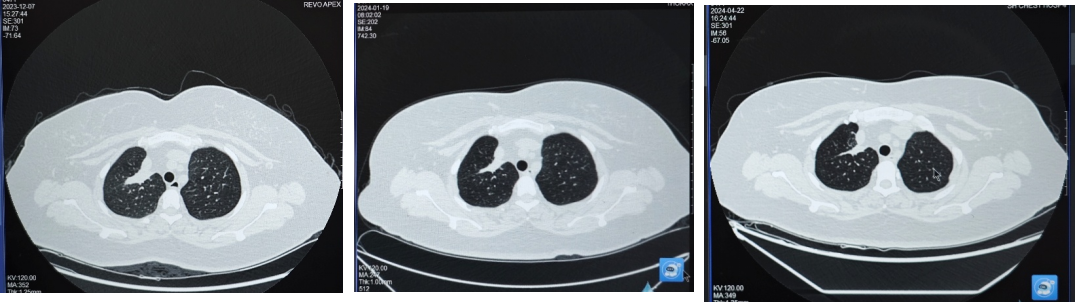

第一阶段:2024年1月19日首次复查,肺部病灶较前缩小,大小约34×11mm;2024年4月22日复查,肺部病灶较老片相仿,疗效评价维持SD,治疗方案调整为“培美曲塞+PD-1单抗+贝伐珠单抗”,并开始使用双膦酸盐进行骨保护治疗。

第二阶段:2024年10月21日,胸部CT示肺部原发灶大小较老片相仿,疗效评价维持SD。在前述全身免疫治疗方案的基础上,于2024年10月起将骨保护药物从双膦酸盐调整为地舒单抗(120mg,Q4W)。

在变更骨保护药物方案前,患者免疫联合治疗达到并维持SD状态约10个月,在使用培美曲塞+PD-1+抗血管药物+地舒单抗后,患者肿瘤再次开始缩小,2025年2月复查胸部CT时,右肺上叶病灶缩小至24×11mm,达到PR。2025年8月复查胸部CT时,右肺上叶病灶进一步缩小至22×6mm,最佳疗效PR